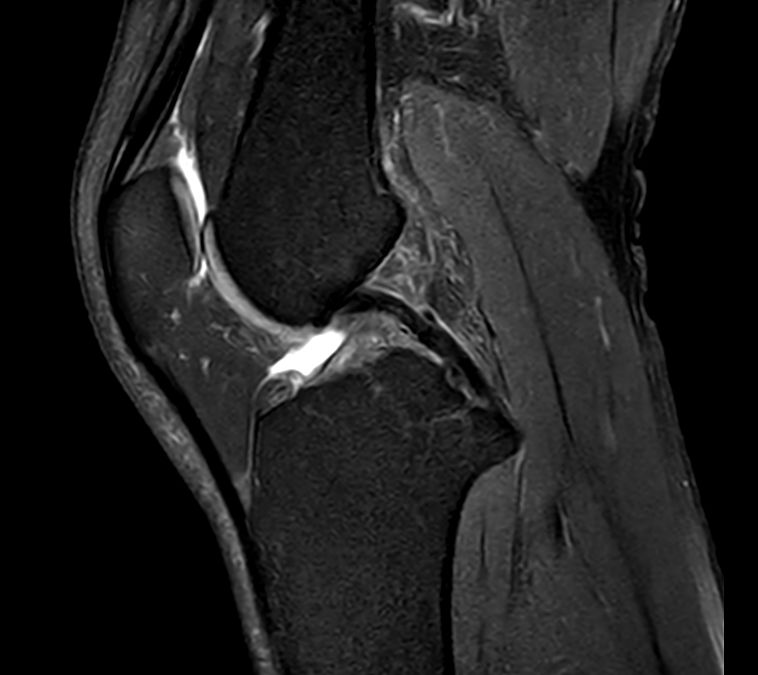

Sagittal PDw TSE

Sagittal PDw TSE FatSat